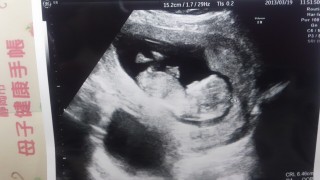

フランスからです。12週5日の時にもらった初めてのエコー写真です。胎児の大きさ67mmでした。12週の精密検査だったので、最後に「何かありますか?」とエコー技師の方に聞いたら「日本の機械はいいねぇー」と言われました。